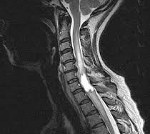

D43.4 Новообразование спинного мозга